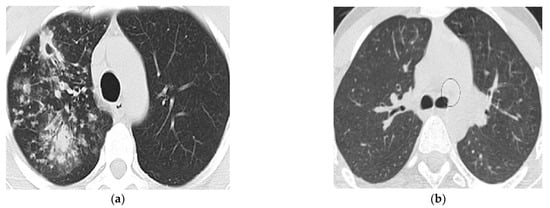

An image taken by CT scan device contains both lungs in almost two halves. Tuberculosis is a bacterial disease that affects the lungs badly; however, it is not necessarily both lungs simultaneously. It might be possible that one lung is infected badly while another lung is functioning normally, or it might be the case that both lungs are infected equally, or sometimes one lung is damaged more rapidly than the other one. Due to the non-linear spread of TB infection, it is impossible to count the whole CT scan image as a region of interest. Choosing only the infected lung area for abnormal and non-infected areas for a normal case study would ensure more precision and accuracy of the developed system for classification. In our research ROI size was kept uniform for both cases was 32 × 32 in a circle shape. Abnormal CT scan images are shown in Figure 4.

Figure 4. ROIs selection ((a): Abnormal lung’s CT scan image and (b): 3 ROIs).